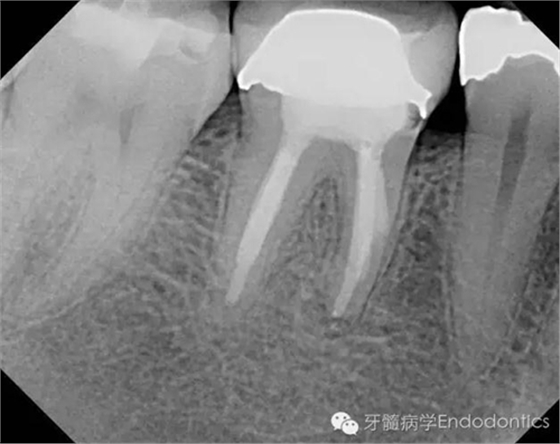

圖5.根充后X線片

圖6.隨訪兩年后X線片